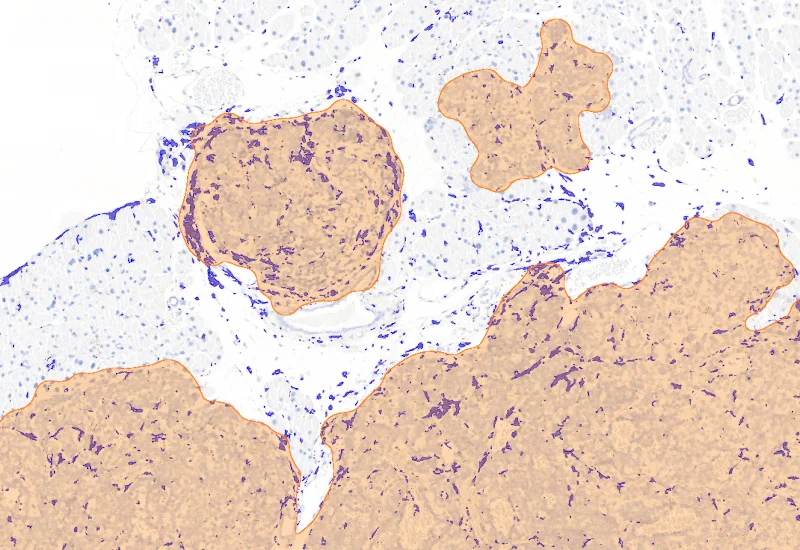

IHC Tumor Macrophages

Segment tissue into tumor and healthy areas, detect CD68+ macrophages, and quantify macrophage area within each tissue compartment.

The IHC Tumor-Macrophages APP provides tissue detection including separation into tumor tissue and healthy tissue. It detects macrophages based on a specific staining (e.g. CD68). The APP outputs the area of macrophages within tumor tissue and healthy tissue.

Image courtesy of Dr. Patrick Michl, Dr. Maren Egidi and Dr. Heidi Griesmann, Universitätsklinikum Halle (Saale)